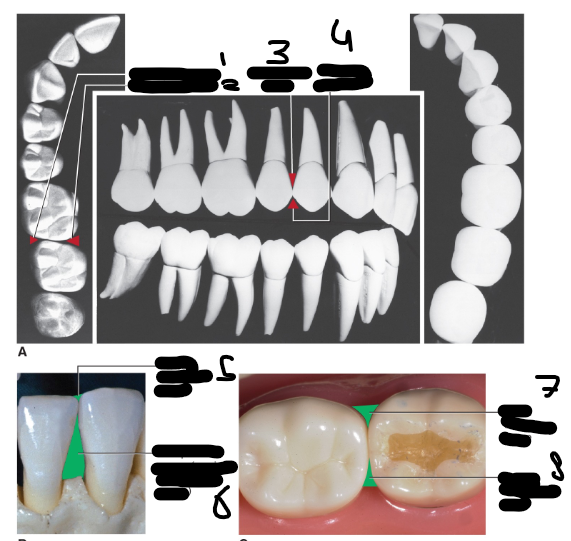

Sulcus gingivalis (mogelijke ruimte), Gingival sulcus (Afbeelding)(Intro parodontium)

1

Margo gingivalis, Tandvleesrand, Gingival margin (Afbeelding)(Intro parodontium)

2

Cementum van de wortel, Cementum of root (Afbeelding)(Intro parodontium)

3

Gingiva libera, Vrije gingiva, Free gingiva (Afbeelding)(Intro parodontium)

4

Gingiva adherens, Aangehechte gingiva, Attached gingiva (Afbeelding)(Intro parodontium)

5

Ligamentum parodontale, Parodontaal ligament, Periodontal ligament (Afbeelding)(Intro parodontium)

6 (in de mond veel kleiner)

Processus alveolaris, Alveolair bot, Alveolar Bone (Afbeelding)(Intro parodontium)

7

Gingiva adherens, Aangehechte gingiva, Attached gingiva (Afbeelding)(Parodontium, kliniek)

Gingiva libera (over the mogelijke ruimte: sulcus gingivalis), Vrije gingiva, Free gingiva (Afbeelding)(Parodontium, kliniek)

Margo gingivalis, Tandvleesrand, Gingival margin (Afbeelding)(Parodontium, kliniek)

Papilla interdentalis, Interdentale papil, Interdental papilla (Afbeelding)(Parodontium, kliniek)